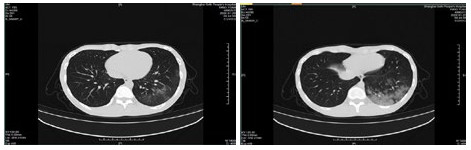

| 图 6 患者,女性,55岁,既往体健,沪籍,无明确武汉流行病学接触史。发热6 d,伴咳嗽,体温39.4℃,伴肌肉酸痛,流感病毒A型IgM阳性,抗柯萨奇病毒IgM阳性,新型冠状病毒核酸检测阴性。肺部CT提示双肺散在磨玻璃结节,部分贴近胸膜。诊断甲型流感病毒性肺炎 Fig 6 Case 6, female, 55 years old, born in Shanghai, was physically healthy, and had no clear history of epidemic exposure of Wuhan. She had fever for 6 days, body temperature was 39.4 ℃, with cough, muscle ache, positive influenza A IgM and anti Coxsackie IgM, negative novel coronavirus nucleic acid test. Lung CT showed ground glass nodules were scattered in bilateral lungs, some of which were close to pleura. She was diagnosed as influenza A virus pneumonia |

| 图 7 患者,女性,36岁,沪籍,有武汉流行病学接触史。发热8 d伴咳嗽,咳痰,有头胀痛,体温38.5℃, 白细胞总数21.8×109/L,淋巴细胞计数10.4%,甲型流感筛查阴性,流感病毒B型IgM阳性,新型冠状病毒核酸检测2次阴性。肺部CT提示双肺多发团片影,实变及磨玻璃结节,伴支气管充气征。诊断乙型流感病毒性肺炎 Fig 7 Case 7, female, 36 years old, born in Shanghai, with a history of epidemic exposure of Wuhan. She had fever for 8 days with cough, expectoration, head pain, body temperature of 38.5℃, total white blood cells of 21.8×109/L, lymphocyte count of 10.4%, negative influenza A virus screening, positive influenza B IgM, and negative novel coronavirus nucleic acid test for twice. Lung CT showed multiple mass shadows, consolidation and ground glass nodule in both lungs, accompanied by bronchiectasis. She was diagnosed as influenza B pneumonia |

| 图 8 患者,男性,20岁,湖北籍,发病前6 d有武汉流行病学接触史,发热,体温39.3℃,有干咳,血白细胞总数及淋巴计数正常,甲型、乙型流感病毒抗原筛查阴性以及其他呼吸道常规病毒筛查阴性,新型冠状病毒核酸检测2次阴性。肺部CT提示左下肺磨玻璃结节,贴近胸膜,可见铺路石征,小叶间胸膜增厚。病因不明 Fig 8 Case 8, male, 20 years old, born in Hubei Province, had a history of epidemic exposure of Wuhan 6 days before the onset of the disease. He had fever with a body temperature of 39.3 ℃, dry cough, normal WBC and lymph count, negative influenza A and B virus screening, and other routine respiratory virus screening, negative novel coronavirus nucleic acid test for twice. Lung CT showed ground glass nodule of the lower left lung, close to the pleura, with paving stone sign and thickening of interlobular pleura. Unknown etiology |